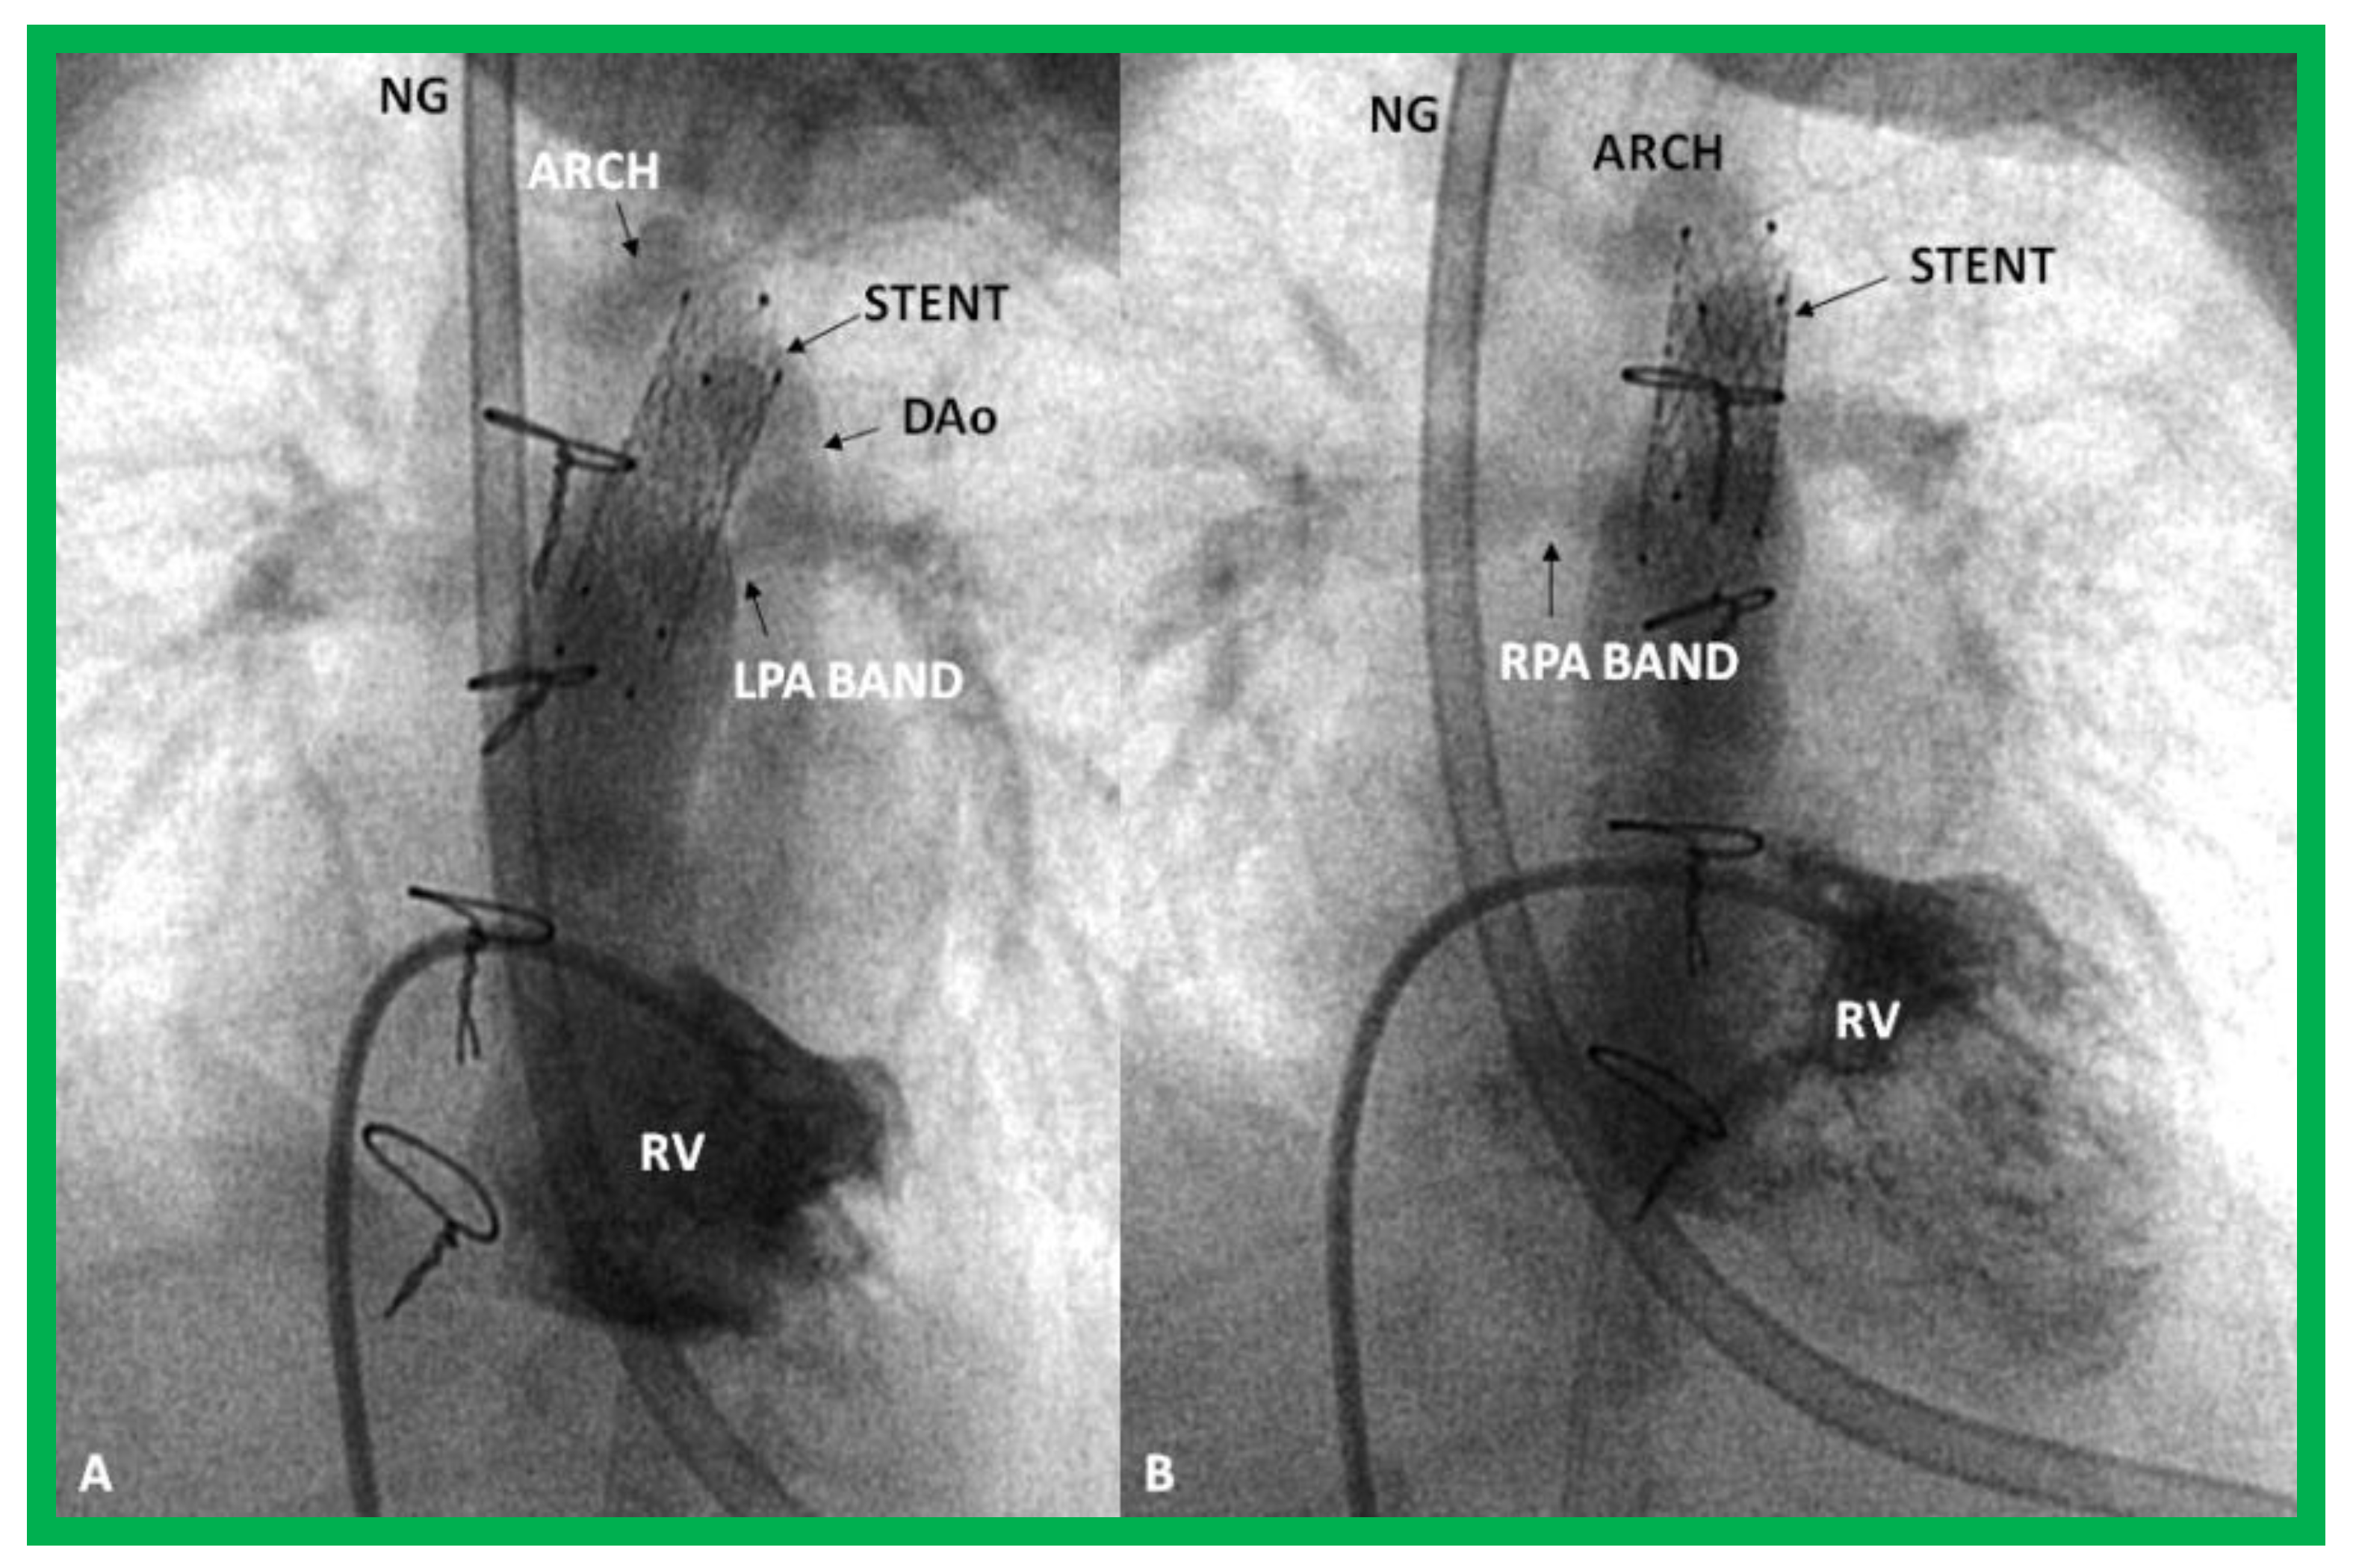

Figure 31.

Selected cine frames in sitting-up (A) and right anterior oblique (B) views from a right ventricular (RV) angiogram, demonstrating the position of a stent (STENT) placed within the ductus via a purse-string suture in the pulmonary artery during a hybrid procedure, in a premature infant with hypoplastic left heart syndrome shown in Figure 30. Note the opacification of the descending aorta (DAo) via the stent. Bands placed during the hybrid procedure around the right (RPA) (in B) and left (LPA) (in A) pulmonary arteries are seen. ARCH, aortic arch opacified retrogradely via the STENT. NG, naso-gastric tube.

During stage II, aortic arch reconstruction, atrial septectomy, and a bidirectional Glenn shunt are performed. This is followed by a Fontan conversion (Stage III). It would appear that there is a reduction of early mortality when this approach is used, but some of it is transferred to Stage II. A careful comparison of the hybrid approach with the conventional Norwood procedure did not reveal an improvement in outcome following the hybrid procedure [128]. In addition, a lower systemic and cerebral oxygen delivery with the hybrid procedure than with the Norwood procedure [129] is of concern. It appears that the majority of institutions are reverting to a conventional Norwood procedure with a Sano shunt. Our own personal preference is to reserve the hybrid procedure for premature babies with HLHS and those that have other co-morbidities that preclude safe Norwood palliation.